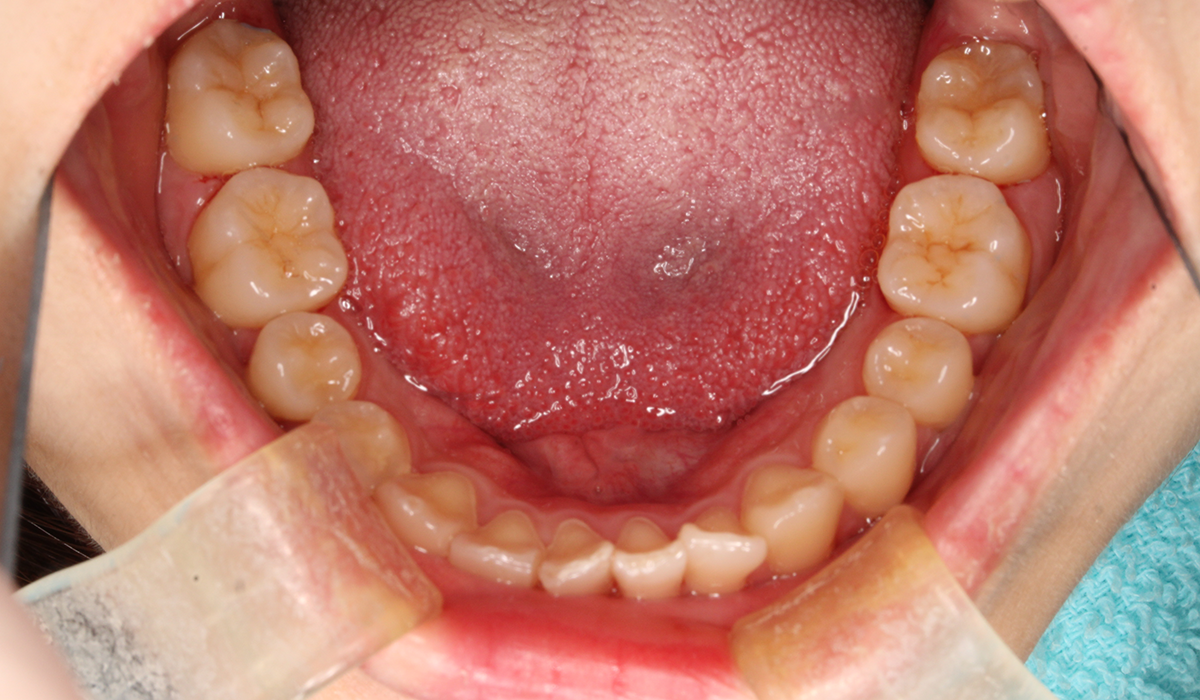

下顎

術前